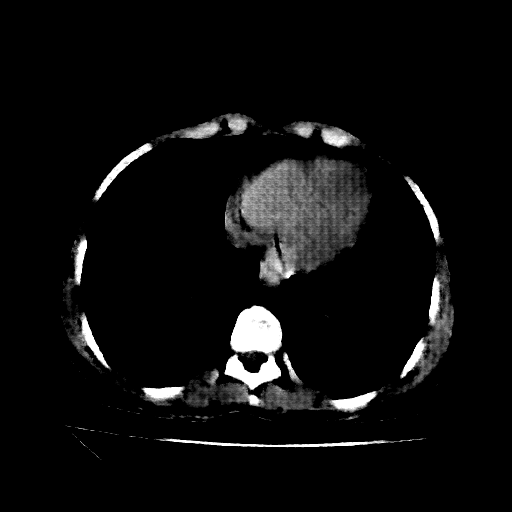

Slice 70 Targeting Evaluation

Slice: Slice_70

Conversion: NATIVE β†’ VENOUS

Original NATIVE CT scan (input)

No window - Raw intensity values